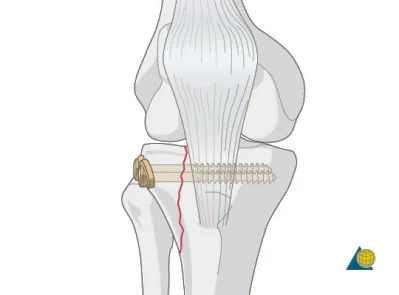

| Screws | Good fixation – stable – Can apply good inter‑fragmentary compression In simple fractures Can be applied percutaneous | ![]() ![]() |